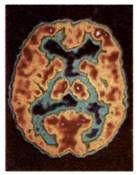

Η νόσος αυτή προσβάλλει στις ανεπτυγμένες χώρες το 5% των ατόμων ηλικίας πάνω από 65 ετών και το 20% των ατόμων ηλικίας πάνω από 80 ετών. Οδηγεί στην άνοια (προοδευτική απώλεια των πνευματικών λειτουργιών, ανεξάρτητη από αυτήν που συνοδεύει τη γήρανση του εγκεφάλου). Τα άτομα που προσβάλλονται από τη νόσο εμφανίζουν απώλεια μνήμης, μειωμένη ικανότητα σκέψης και λογικής αιτιολόγησης, δυσκολίες στην επικοινωνία με άλλα άτομα, ακόμα και ανικανότητα στην εκπλήρωση απλών καθημερινών

δραστηριοτήτων. Στους πάσχοντες παρατηρήθηκαν ανωμαλίες σε νευρώνες, κυρίως σε περιοχές του φλοιού των ημισφαιρίων. Στις περιοχές αυτές παρατηρούνται εξωκυτταρικές εναποθέσεις (αμυλοειδείς πλάκες), λόγω συσσώρευσης μίας μικρού μοριακού βάρους πρωτεΐνης, της β-αμυλοειδούς πρωτεΐνης. Η αυξημένη συγκέντρωση της πρωτεΐνης αυτής οδηγεί πιθανώς στη λύση των λυσοσωμάτων, με συνέπεια την καταστροφή των νευρικών κυττάρων. Η πρωτεΐνη αυτή αποτελεί τμήμα μιας άλλης πρόδρομης πρωτεΐνης, της ΑΡΡ (Amyloid Precusor Protein), που φυσιολογικά βρίσκεται στην κυτταρική μεμβράνη των νευρώνων και άλλων κυττάρων. Μία μορφή της νόσου φαίνεται να είναι κληρονομική. Έχει απομονωθεί γονίδιο στο 21ο ζεύγος των χρωμοσωμάτων, το οποίο καθορίζει τη δομή της πρόδρομης πρωτεΐνης. Η γονιδιακή αυτή θέση αποκτά ιδιαίτερο ενδιαφέρον, διότι όλα σχεδόν τα άτομα που πάσχουν από το σύνδρομο Down (τρισωμία 21) και επιβιώνουν μετά τα 35 έτη εμφανίζουν συμπτώματα της ασθένειας Alzheimer.

Απεικόνιση PET εγκεφάλου

υγιή ενήλικα (αριστερά) και

ασθενή που πάσχει από νόσο Alzheimer (δεξιά).

Η αυξημένη επιφάνεια

σκουρόχρωμων περιοχών

στην εικόνα δεξιά δείχνει

διαταραχές στην εγκεφαλική δραστηριότητα